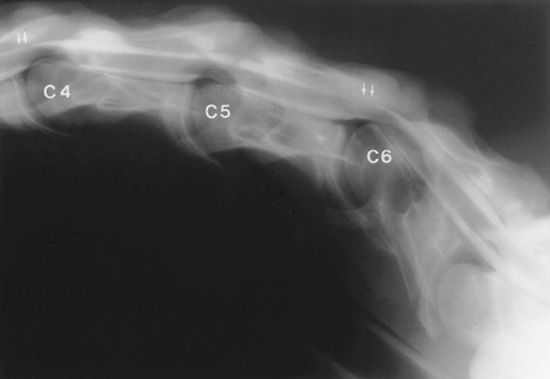

Survey radiographs of the cervical spine are obtained in standing, sedated horses. Cervical radiographs are evaluated by subjective assessment of vertebral malformation and objective determination of vertebral canal diameter.1878 The five categories of cervical malformation subjectively assessed in horses with CVSM are DJD of the articular processes, subluxation between adjacent vertebrae, flare of the caudal physis of the vertebral body, abnormal ossification patterns, and caudal extension of the dorsal laminae1878,1880 (Figs. 35-26 and 35-27). Although the presence of characteristic vertebral malformations supports the diagnosis of CVSM, subjective evaluation of survey radiographs does not reliably discriminate between horses affected and those unaffected by CVSM.1868,1878 DJD of the articular processes of the caudal cervical vertebrae is the most common and severe malformation observed in affected horses.1878 However, degenerative arthropathy occurs in 10% to 50% of nonataxic horses and is the most common and severe vertebral malformation in horses without CVSM.1869,1878 Subjective evaluation of degenerative arthropathy of the articular processes may lead to a false-positive diagnosis of CVSM.1868

Fig. 35-26 Survey radiograph of fifth (C5) and sixth (C6) cervical vertebrae. Bony malformations include flare of the caudal physis (curved arrow, C5), caudal extension of the dorsal lamina (small arrows, C5), and subluxation and malalignment of the C5-C6 articulation. Solid line, Intervertebral canal diameter of C5-C6 articulation; double-headed arrow, intravertebral canal diameter of C5.